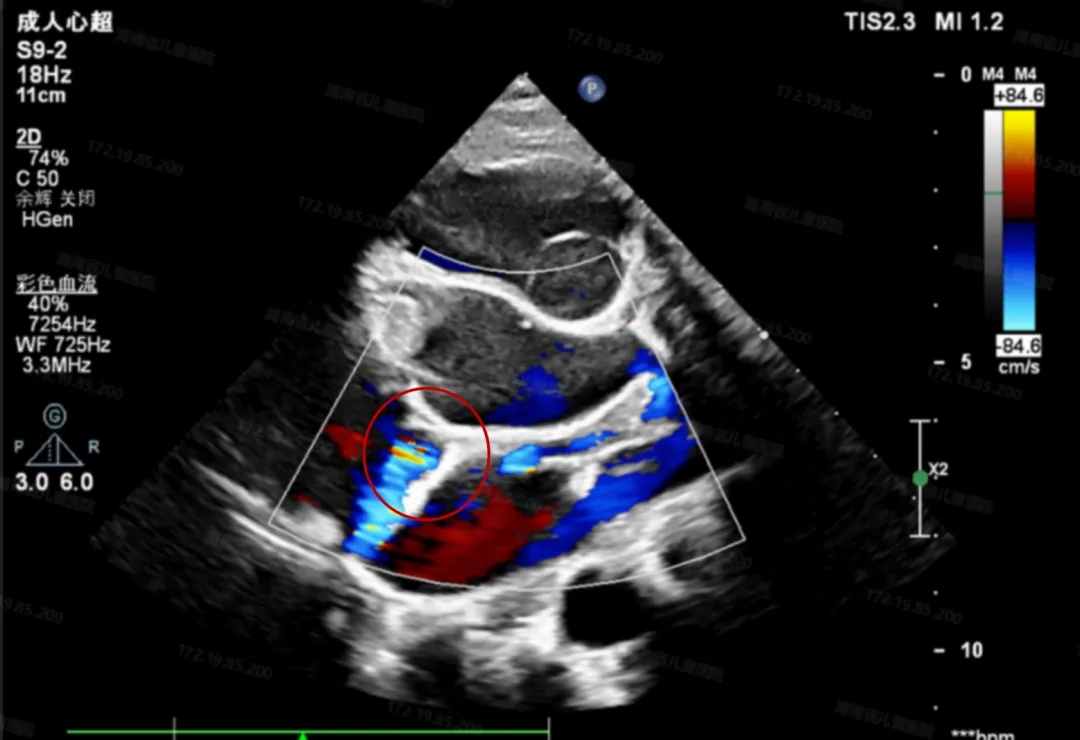

术前超声检查

右心房后壁侧可见高速紊乱的血流信号

左回旋支向右发出一支血管前走行汇入右心房